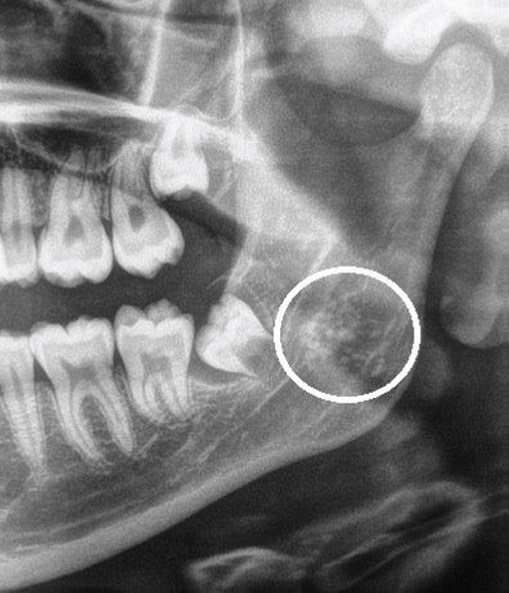

5) Identify the encircled asymptomatic radiopacity in a 38-year-old patient where in the medical history was non-contributory.